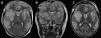

Acute fulminant cerebral edema is a type of rapidly progressive encephalitis that occurs in children and is associated with significant morbidity and mortality.

We present a clinical case with seizures, rapid neurological deterioration and the early appearance of cerebral herniation signs. Although the radiological tests were initially normal and there are no established parameters that predict the evolution of encephalitis to a rapidly progressive subtype, the clinical evolution forced to consider the decompressive craniectomy due to the lack of response to the medical management of the cerebral edema. It may be necessary take a brain biopsy to confirm the etiology of the encephalitis origin of acute fulminant cerebral edema. The objective of surgery should be not only to increase survival, but also to reduce subsequent neurological sequelae.